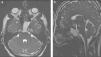

The most common site of CSF leakage is the floor of the anterior cranial fossa, and less commonly in the sphenoid sinus. Only 3-4% of CSF fistulas are spontaneous. The fourth case is presented of a CSF rhinorrhea due to a transclival meningocele, an extremely rare location for these lesions, and the surgical approach. The patient is a 39-year-old male with no history of trauma, and a recent history of watery rhinorrhe and meningitis. CT scan and MRI showed clival bone defect and trans-sphenoidal transclival meningocele. The defect was repaired by transclival trans-sphenoidal endoscopic endonasal approach with good results.

Despite the rarity of transclival meningocele, it is recommended to consider it in the differential diagnosis of spontaneous nasal fistulas. The endoscopic endonasal approach is a direct technique that provides satisfactory results in the resolution of CSF rhinorrhea.